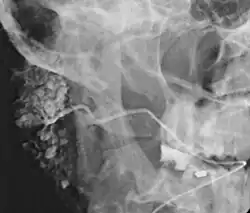

![]() Sialogram in a patient suspected of Sjögren's syndrome | |

Sialography (also termed radiosialography) is the radiographic examination of the salivary glands. It usually involves the injection of a small amount of contrast medium into the salivary duct of a single gland, followed by routine X-ray projections.[1]

The resulting image is called a sialogram.

This procedure is indicated when there is recurrent swelling and pain on the face but ultrasound has not revealed any problems. If Sjögren syndrome (also known as Sicca syndrome, an autoimmune disease that affects the lacrimal and salivary glands, causing reduced tears and saliva production) is suspected, this procedure is useful. Besides, when interventional procedure is planned such as stone removal from salivary ducts or dilatation of the strictures in the salivary gland, this procedure is also indicated.[4] However, for those who are pregnant, with allergy to iodinated contrast, and ongoing infection or inflammation of the face, the procedure is contraindicated.[4]

This study is interpreted by evaluating the morphology of the salivary ducts for obstructions and chronic inflammation. Sialodochitis is a term describing dilation of the ducts caused by repeated inflammatory or infective processes. There is also irregular salivary duct stricture (narrowing) of the duct, which creates an appearance known as "sausage link" pattern on a sialogram. Suggestions of abscesses and autoimmune diseases such as Sjögren syndrome can also be elicited. Sialadenitis is inflammation of the salivary glands, which may cause acinar atrophy and create an appearance known as "pruning of the tree" on a sialogram, where there are less branches visible from the duct system. A space occupying lesion that occurs within or adjacent to a salivary gland can displace the normal anatomy of the gland. This may create an appearance known as "ball in hand" on an sialogram, where the ducts are curved around the mass of the lesion.[6]